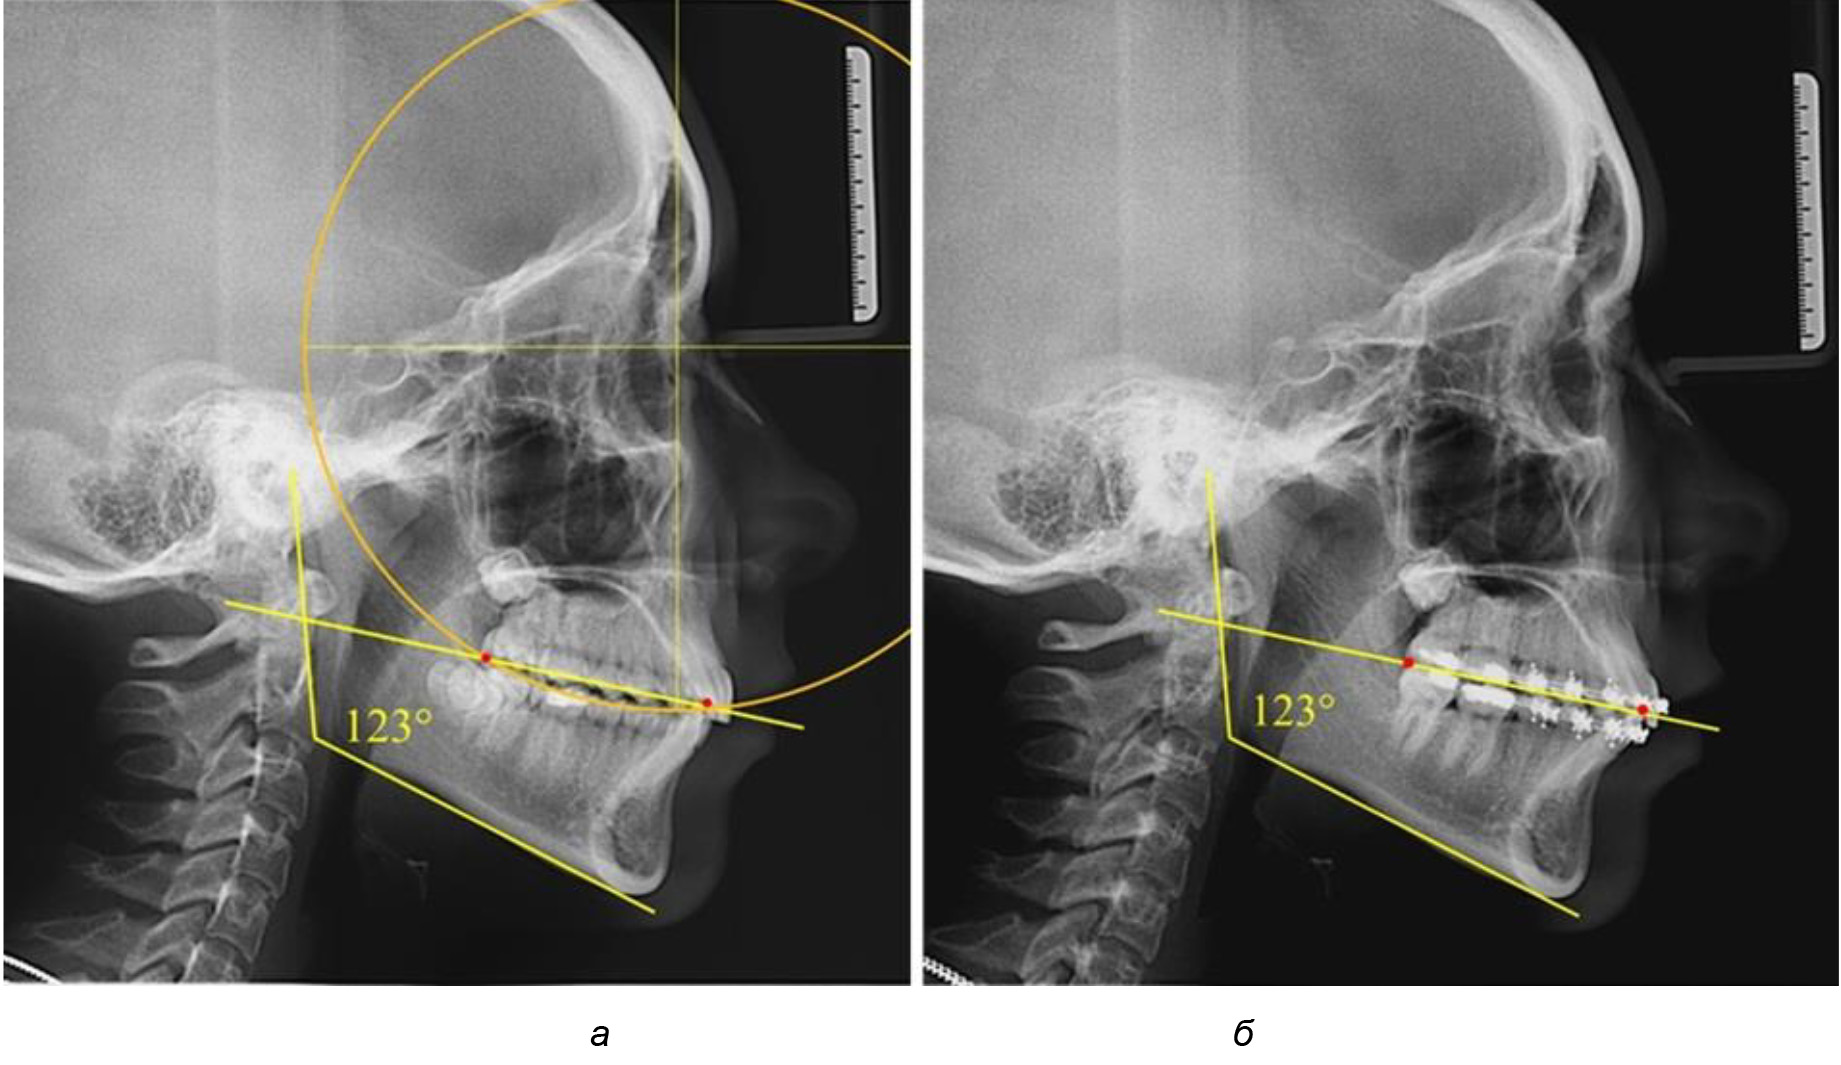

Во 2-й подгруппе 2-й группы было обследовано 7 человек.

Указанная величина не имела достоверного отличия с 1-й подгруппой (р ˃ 0,05), что определяло однородность групп по количественному признаку.

Обращает на себя внимание, что глубина кривой Spee в анализируемой подгруппе практически не отличалась от показателей, полученных у людей с физиологической окклюзией, и составляла (4,23 ± 1,58) мм. Отношение радиуса окружности к сагиттальному размеру окклюзионной линии в среднем по подгруппе составляло 1,623 ± 0,02 и соответствовало числу Фибоначчи.

После лечения пациентов техникой «прямой» дуги, так же как и в 1-й подгруппе, было отмечено увеличение сагиттального размера окклюзионной лини в среднем на (2,38 ± 0,83) мм. Окклюзионная линия практически касалась окклюзионного контура всех жевательных зубов, и отмечалось практически полное отсутствие кривой Spee, так же как и у людей 1-й подгруппы 2-й группы (рис. 6).

Рис. 6. Особенности ТРГ при оптимальной кривой Spee до лечения (а) и после лечения (б) техникой «прямой» дуги

Таким образом, проведенное лечение техникой «прямой» дуги способствует нормализации окклюзионного равновесия и торку передних зубов, однако не соответствует оптимальному окклюзионному статусу, характеризующему физиологическую окклюзию. При этом величина нижнечелюстного угла оставалась на прежнем уровне.